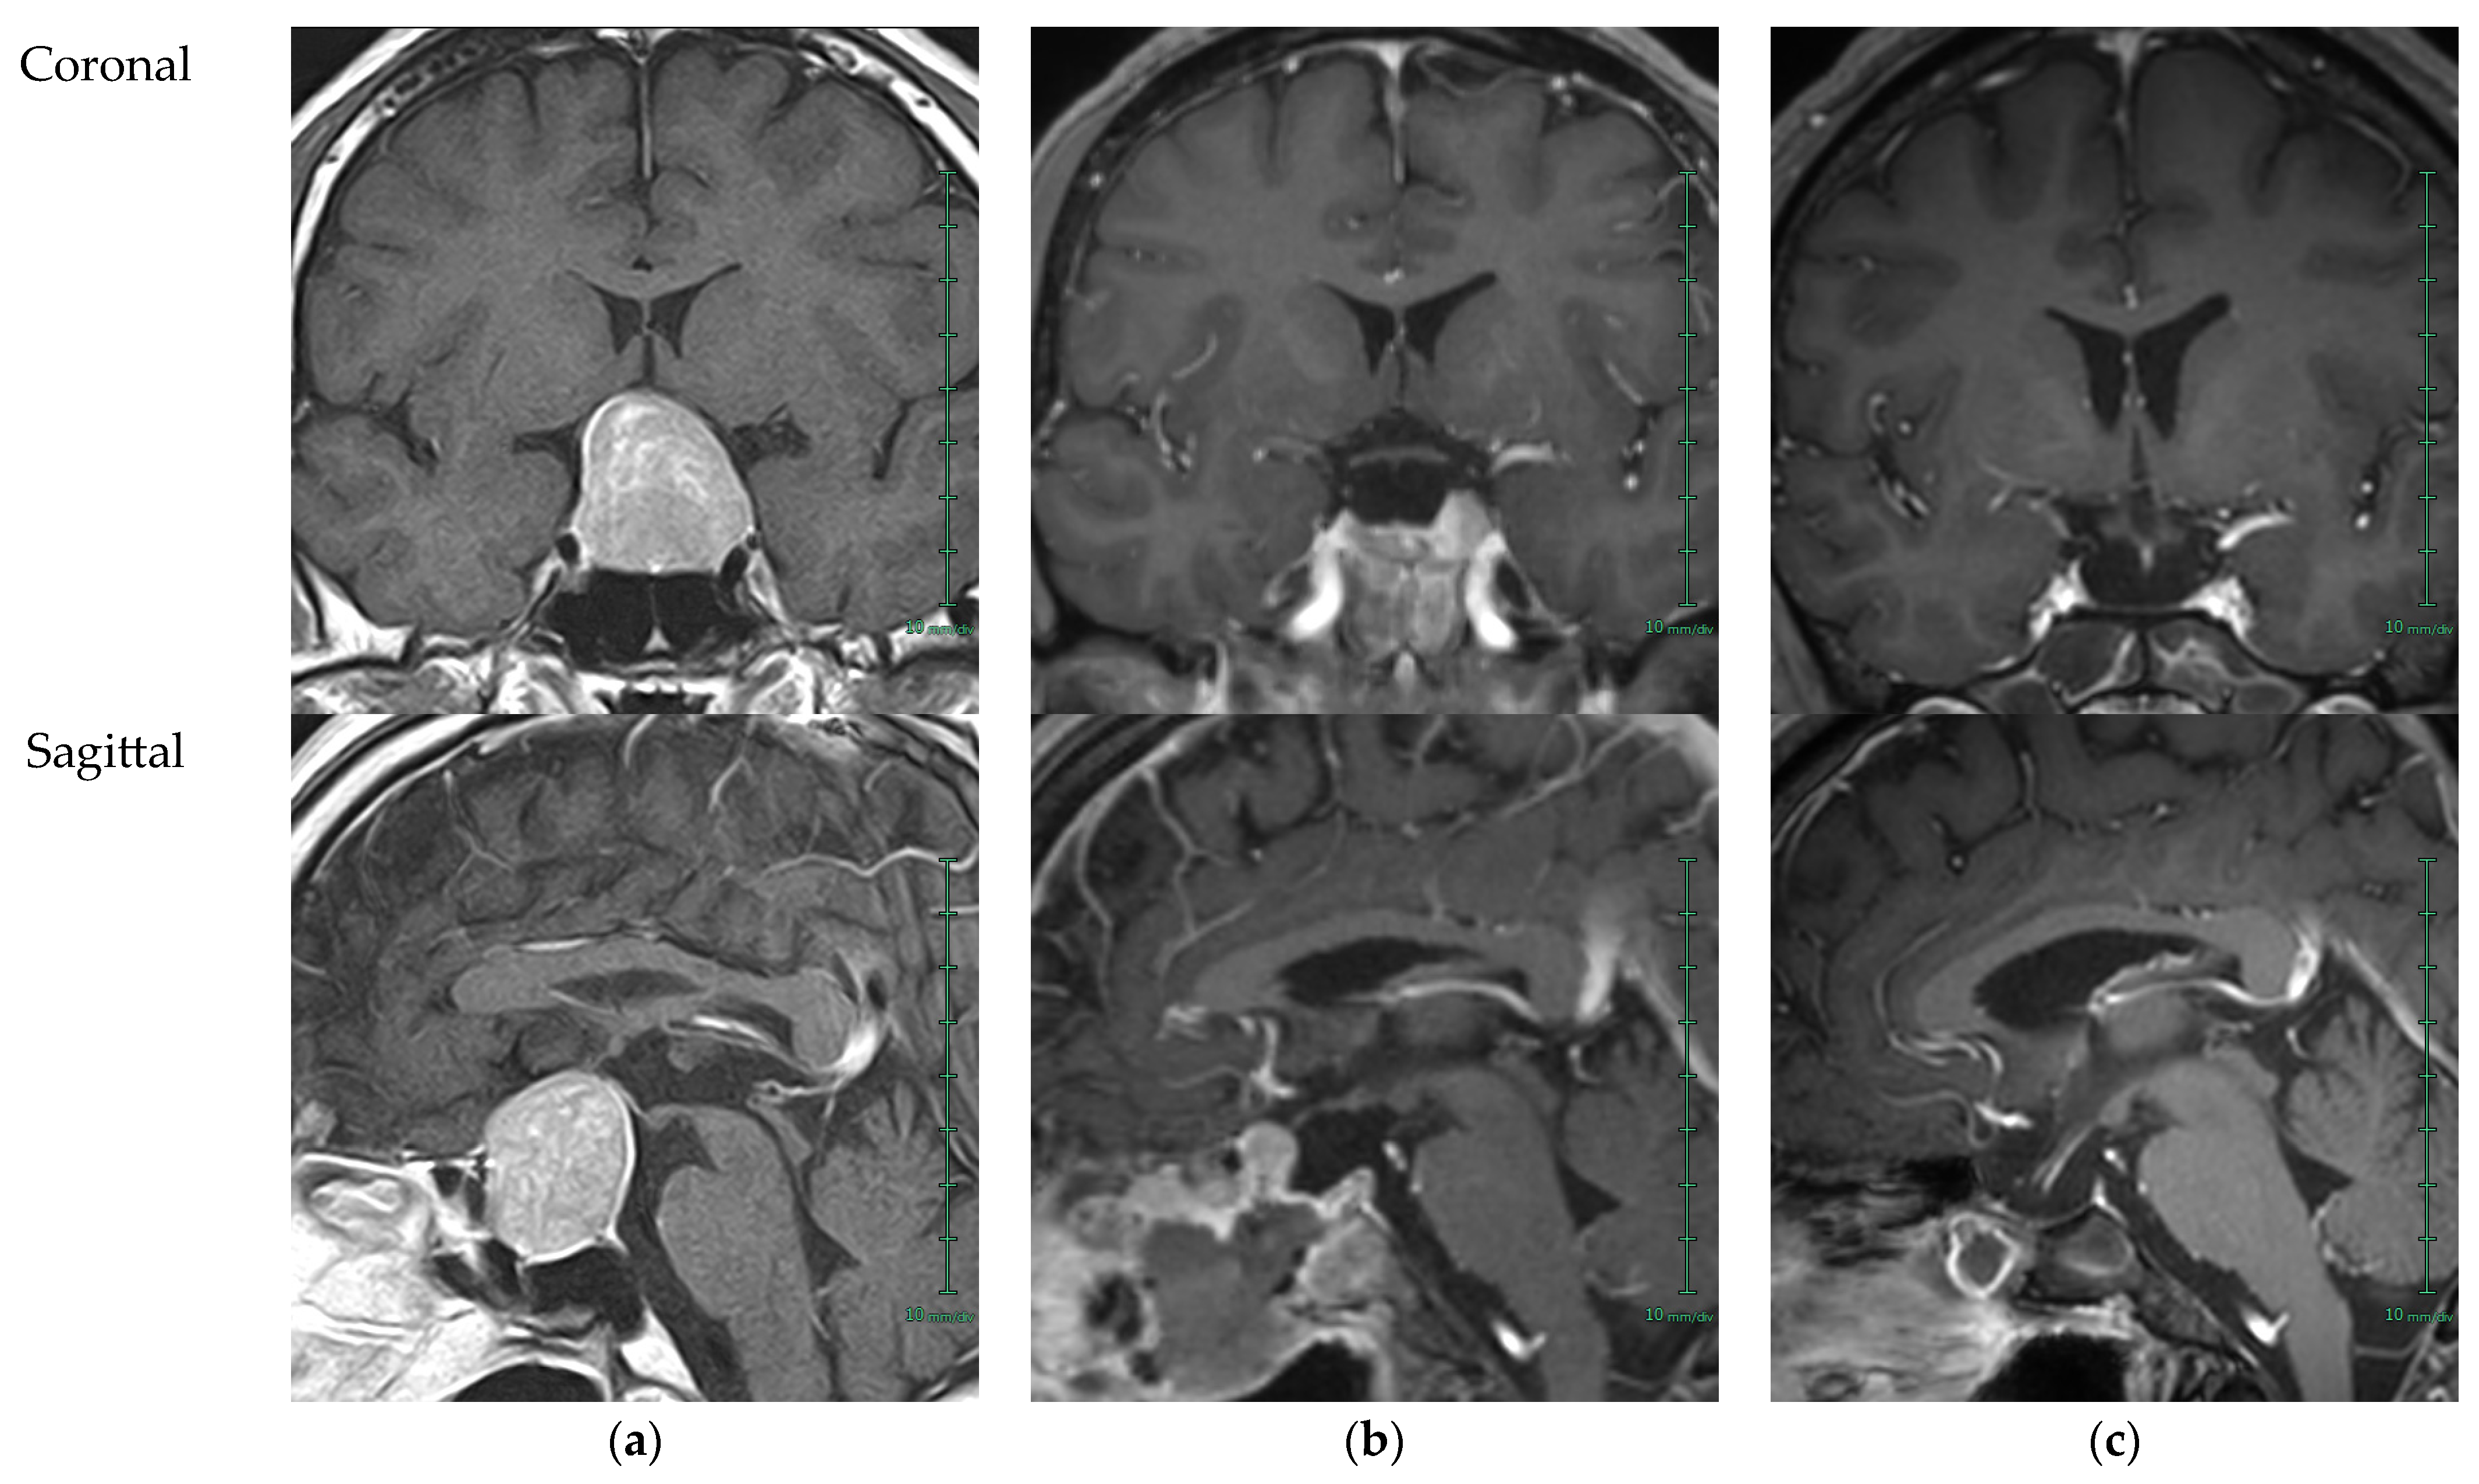

2. Case Presentation